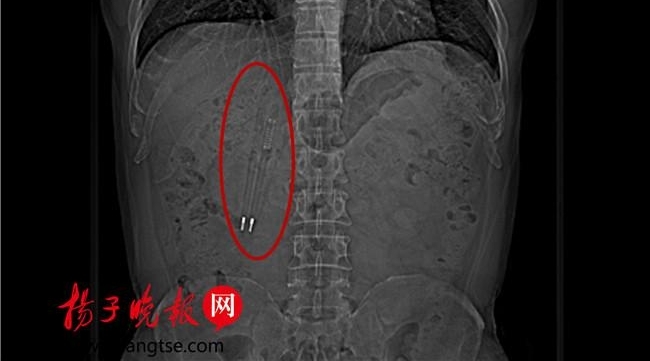

王先生体内的笔长约12公分,位于十二指肠球降部。昆山中医院消化内科主任徐宏伟介绍说,这个笔从口中吞下,经过了食管、胃、幽门,到达了十二指肠,其中有一支笔的笔尖已经戳到了肠壁,由于十二指肠长度也仅一支笔的长度左右,笔无法再向下滑。

王先生吞下去的这两支笔都是塑料的,从CT上看,还可以看到笔里的金属弹簧和金属笔尖在闪闪发光。据王先生回忆,他吞下去时,这个笔的外层是红色的,但是,据医生徐宏伟说,取出来的笔的外层已经完全变黑了,但是里面的笔芯还是完好的。